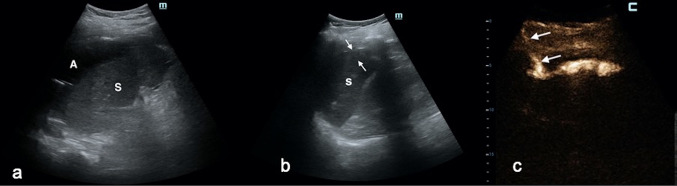

Fig. 2.

a CEUS evaluation (per venam) of a huge multiloculated liver abscess: this scanning modality could not establish whether or not the cavities were communicating. b Before catheter deployment, IC-CEUS via the needle (white arrow) placed in the greatest cavity demonstrated that all cavities were communicating. c A single catheter was positioned. IC-CEUS confirmed that all abscess pouches were communicating, and there was no need to place another drainage

Presence/lack of communication between multiple compartments of fluid collections with consequent treatment decisions. In 3 cases (1 PLA, 1 NIAFC, and 1 IPFC) with enhancement of all cavities, placement of a single catheter was the treatment of choice (Fig. 2). In contrast, in 2 cases (1 PLA and 1 NIAFC), lack of communication induced the operator to aspirate singular PLA loculations instead of perform catheter drainage (an additional session of multiple needle aspirations was thereafter carried out), while in the remaining patient, positioning of two catheters was necessary.